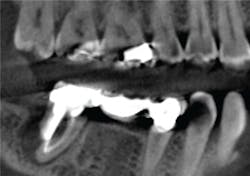

Initially, we evaluate our CBCT scan to give us an understanding of Jane's initial presentation. Similar to panoramic imaging, this "birds-eye" view is critical during the new-patient exam to help us prioritize Jane's treatment needs. Often, clinicians get hung up on "filling the hole." Sirona 3-D imaging provides a roadmap to comprehensive diagnostics. Jane's bridge, despite being asymptomatic, presents with a large periapical radiolucency. We suspect a root fracture from the endodontic post and note that No. 31 has a poor long-term prognosis and is not a candidate for re-treatment.

Our discussion with Jane includes surgical extraction of No. 31 with ridge preservation technique. Once healed, we treatment plan a follow-up CBCT scan, surgical guide, and three endosseous implants at Nos. 30, 31, and the edentulous site, No. 19.

Galileos and CEREC Integration allows perfect case presentation and treatment planning on the first appointment. This creates a problem-solving approach and facilitates proactive treatment in extracting No. 31 with grafting in preparation for implants. Remember, Jane is asymptomatic at No. 31, but with 3-D imaging for diagnostics and treatment presentation purposes, such treatment is readily accepted. After proper management of site No. 31, a new CBCT scan is obtained for evaluation of bone fill and consideration of IA nerve. We recommend guided surgery for precision and enhanced safety. For guided surgery, we simply obtain a full-arch CEREC optical impression. With this data, can prosthetically plan our implant treatment using CEREC software. With SICAT Optiguide Implant Surgical Guide, there is no need for impressions. The digital data allows Sirona and SICAT to fabricate a surgical guide using a pure digital pathway for guided implant dentistry. Once surgical therapy has been provided, the use of CEREC allows for complete control from chairside abutment and restoration fabrication.

Evaluation of CBCT data allows us to evaluate the TMJ and relative position of the condyle. From this hard tissue imaging, we can assess condylar remodeling and degeneration. In combination with JMT, we rule out joint pathology. With CBCT we are able to confidently rule out overall maxillofacial pathology and confirm health.